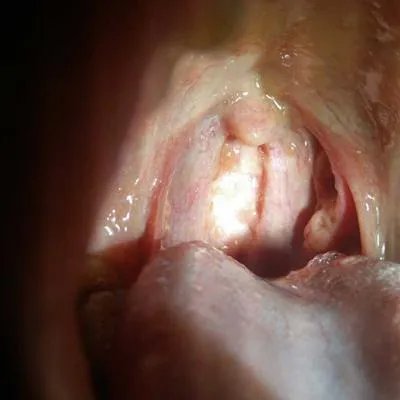

概述 疱疹性咽峡炎是一种非常常见的疾病,一般来说,疱疹性咽峡炎具有很强的传染性,主要是由于患者受到了病毒感染所引起的,而且经常通过粪口途径进行传播,当患者出现疱疹性咽峡炎的时候一定要注意口腔卫生要养成一个良好的饮食习惯,多喝水,多吃一些具有维生素的物质,患者还要在医生的指导下进行一些针对性的治疗,改善患者的临床症状。

疱疹性咽颊炎怎么治疗?

第一:首先当患者患有疱疹性咽峡炎的时候,最重要的治疗方法就是要养成一个良好的口腔习惯,在早晚饭都要注意刷牙,每次吃饭之后要用水进行漱口,患者可以使用淡盐水漱口,如果出现骚痒的时候还可以使用一些抗菌药。

第二:另外当患者患有疱疹性咽峡炎的时候可以使用一些局溃疡的时候可以在局部涂上硝酸银,如果出现发热,这个时候可以针对性地使用些抗菌药物进行治疗。

注意事项一般来说的患者会有了疱疹性咽峡炎的时候,最主要的就是要进行局部的口腔护理保持口腔的清洁,另外患者还可以使用一些局部性的药物,比如说可以使用激素类的或者是使用抗菌药物。